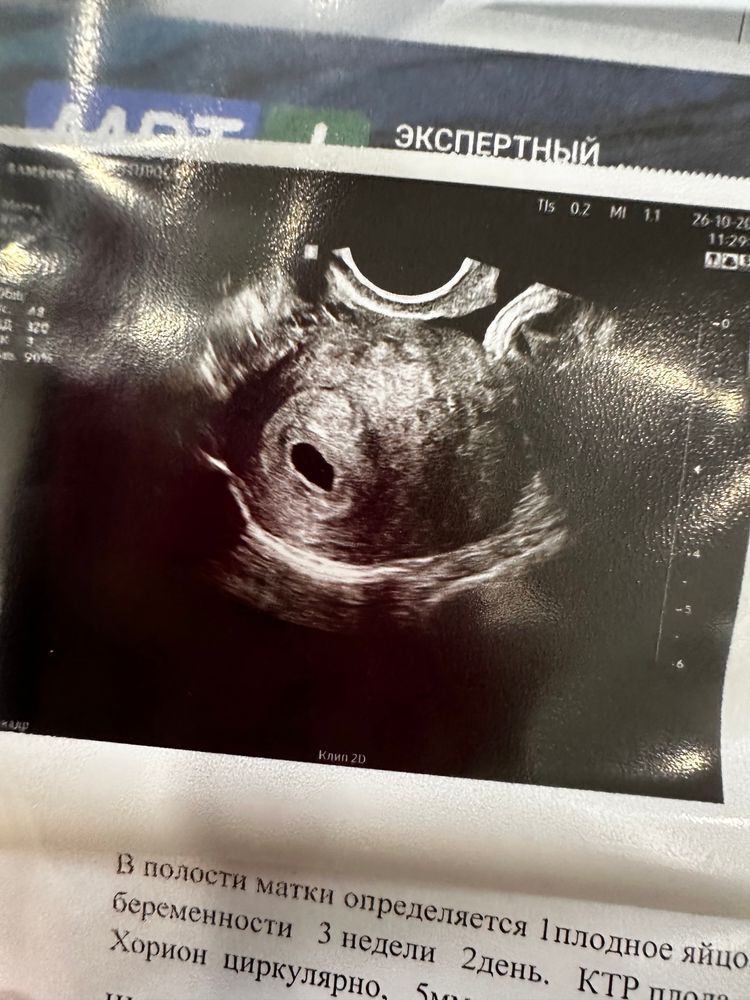

Б есть, она не внематочная, это хорошо) а дальше ждём эмбрион и СБ) растите🤗 рано очень узи сделали

Ника, хотелось подтвердить беременность и быть уверенной что она маточная